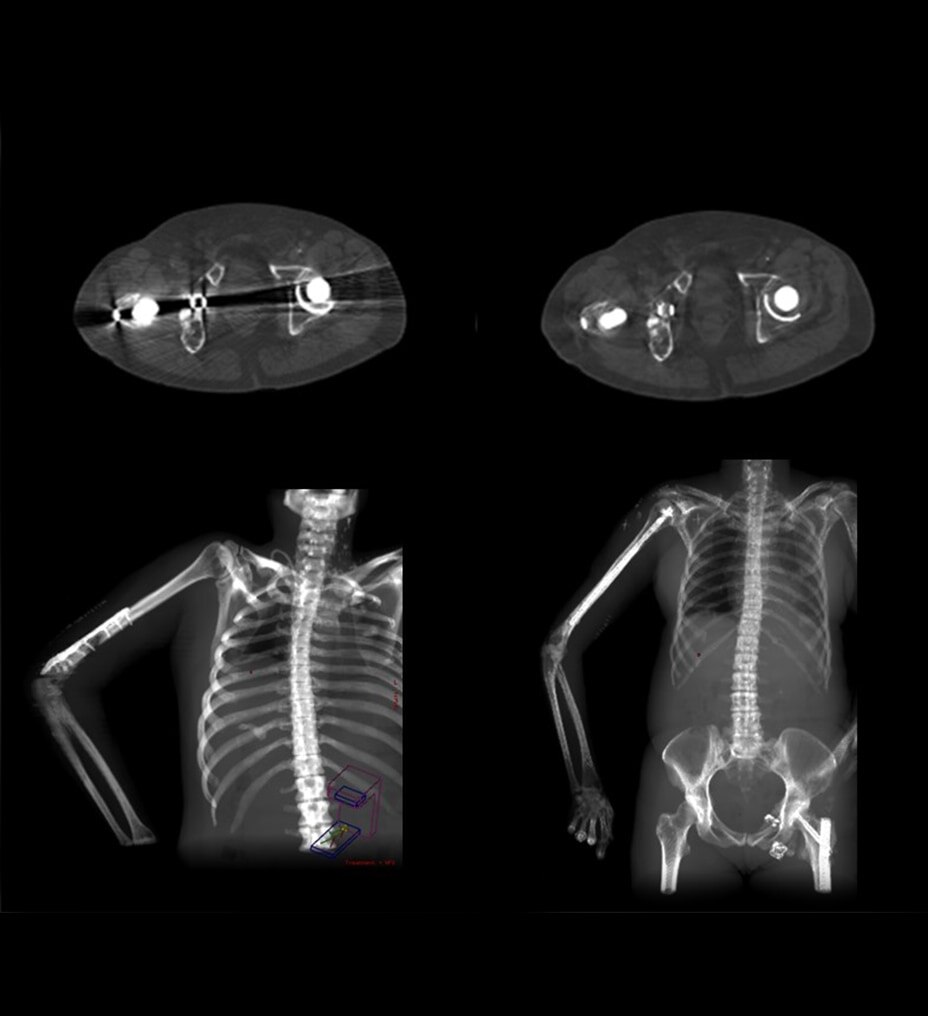

En la RM, los tiempos de adquisición prolongados implican que la adquisición de imágenes se vea comprometida por el movimiento del cuerpo. Hasta ahora. Gracias al aprendizaje profundo, hemos reducido los tiempos de adquisición de minutos a segundos, lo que reduce los artefactos de movimiento y la necesidad de repetir las exploraciones. La aceleración con Sonic DL™ equipa al escáner con la capacidad de igualar la velocidad del cuerpo humano, permitiendo adquisiciones de imágenes que antes no eran posibles.

Construido sobre el éxito revolucionario de AIR™ Recon DL, nuestra primera innovación pionera en la reconstrucción de aprendizaje profundo, Sonic DL™ sigue con audacia sus pasos, avanzando en nuestra misión de revolucionar la RM. El aprendizaje profundo, cuando se aplica a la reducción del tiempo de exploración, convierte los minutos en segundos, lo que ofrece la rapidez de una TC y la calidad de una RM. Es mucho más rápido de lo que permiten las técnicas de aceleración convencionales actuales, lo que ayuda a los radiólogos a realizar diagnósticos precisos desde el principio.

Los departamentos de radiología llevan demasiado tiempo sobrecargados de trabajo. Los tiempos de exploración de RM más rápidos liberan más espacios de turnos y crean flujos de trabajo fáciles de gestionar. Ahora, con un solo ajuste, las configuraciones de la exploración pueden simplificarse. De este modo, se pueden ampliar las capacidades de todos los usuarios. Sonic DL™ está disponible tanto para sistemas 1,5 T y 3 T nuevos como antiguos.

Sonic DL™ permite a los departamentos hacer lo imposible: explorar con precisión a pacientes que antes no se podían explorar de forma eficaz. Ahora, incluso los pacientes enfermos y poco colaboradores pueden someterse a exploraciones en cuestión de segundos, lo que proporciona al personal técnico tiempo libre para realizar el procedimiento con tranquilidad. Al minimizar las posibilidades de movimiento y artefactos que distorsionan las imágenes de exploración, se reduce significativamente la necesidad de volver a realizar exploraciones. Con las exploraciones de un solo latido, los pacientes ya no necesitan contener la respiración, lo que crea una experiencia de exploración más cómoda, tanto para ellos como para el personal técnico que las realiza.